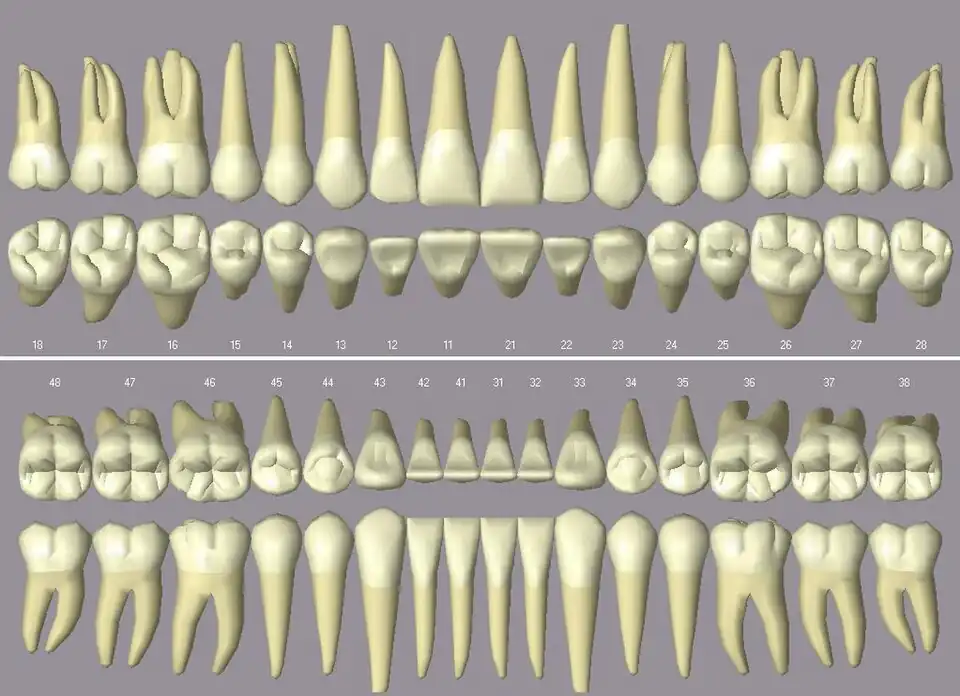

Das menschliche Gebiss (Schema, jeder Zahn in zwei Ansichten)

Die Prämolaren des Menschen haben zwei bis drei Höcker. Untere Prämolaren haben eine sehr ausgeprägte Kronenflucht. Die Anzahl der Zahnwurzeln und Wurzelkanäle ist in der folgenden Tabelle wiedergegeben, wobei Abweichungen möglich sind:[1][2][3]